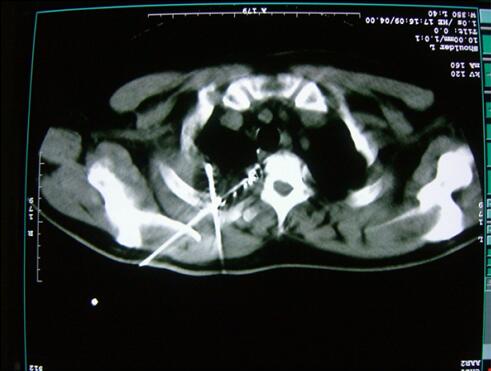

△手术前CT显示

CT检查发现,肿瘤约10×10cm,侵犯到了肋骨和胸膜,徐克成总院长、牛立志院长治疗团队为鲁和平制定的治疗方案是:对肿瘤进行微创冷冻消融,辅以碘粒子植入。术后醒来鲁和平几乎感觉不到痛苦,几天后他就回家准备过年了。